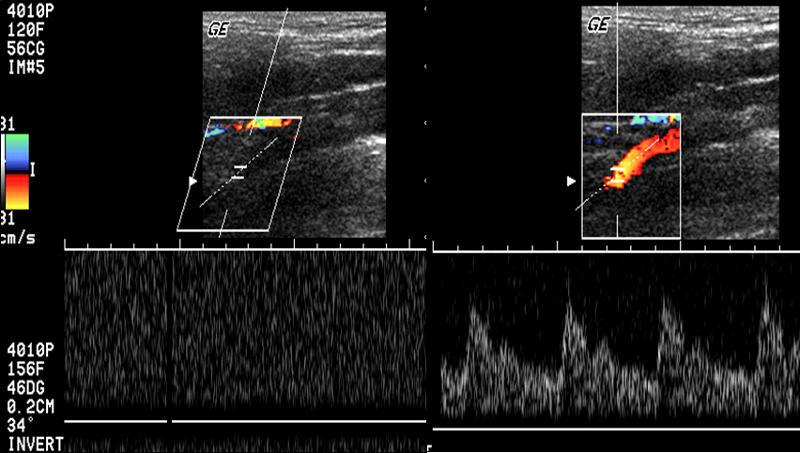

Explain the waveform of the vertebral artery

low resistant

Subclavian steal

abnormal flow direction into the subclavian from the vertebral artery caused by stenosis of the subclavian

- Subclavian artery has a severe stenosis or occlusion

- Vertebral artery must compensate for the reduction of flow

- Becomes a collateral pathway to the extremity

- RETROGRADE flow or abnormal flow present in the vertebral arter